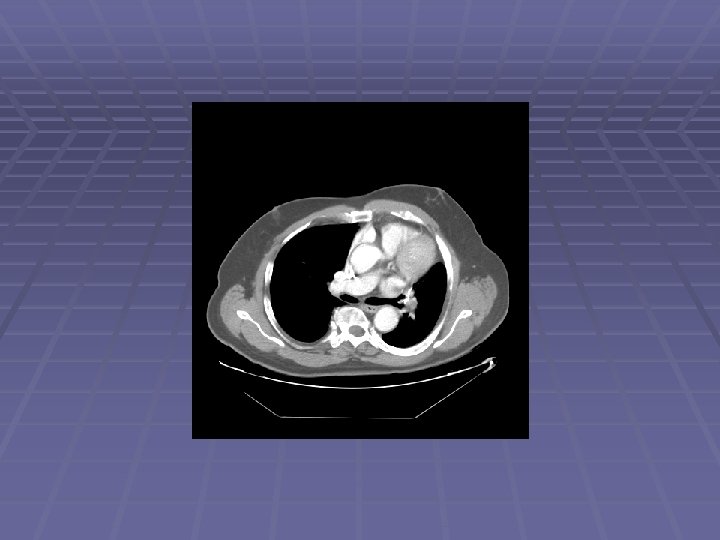

Pancreatic Mass at CT